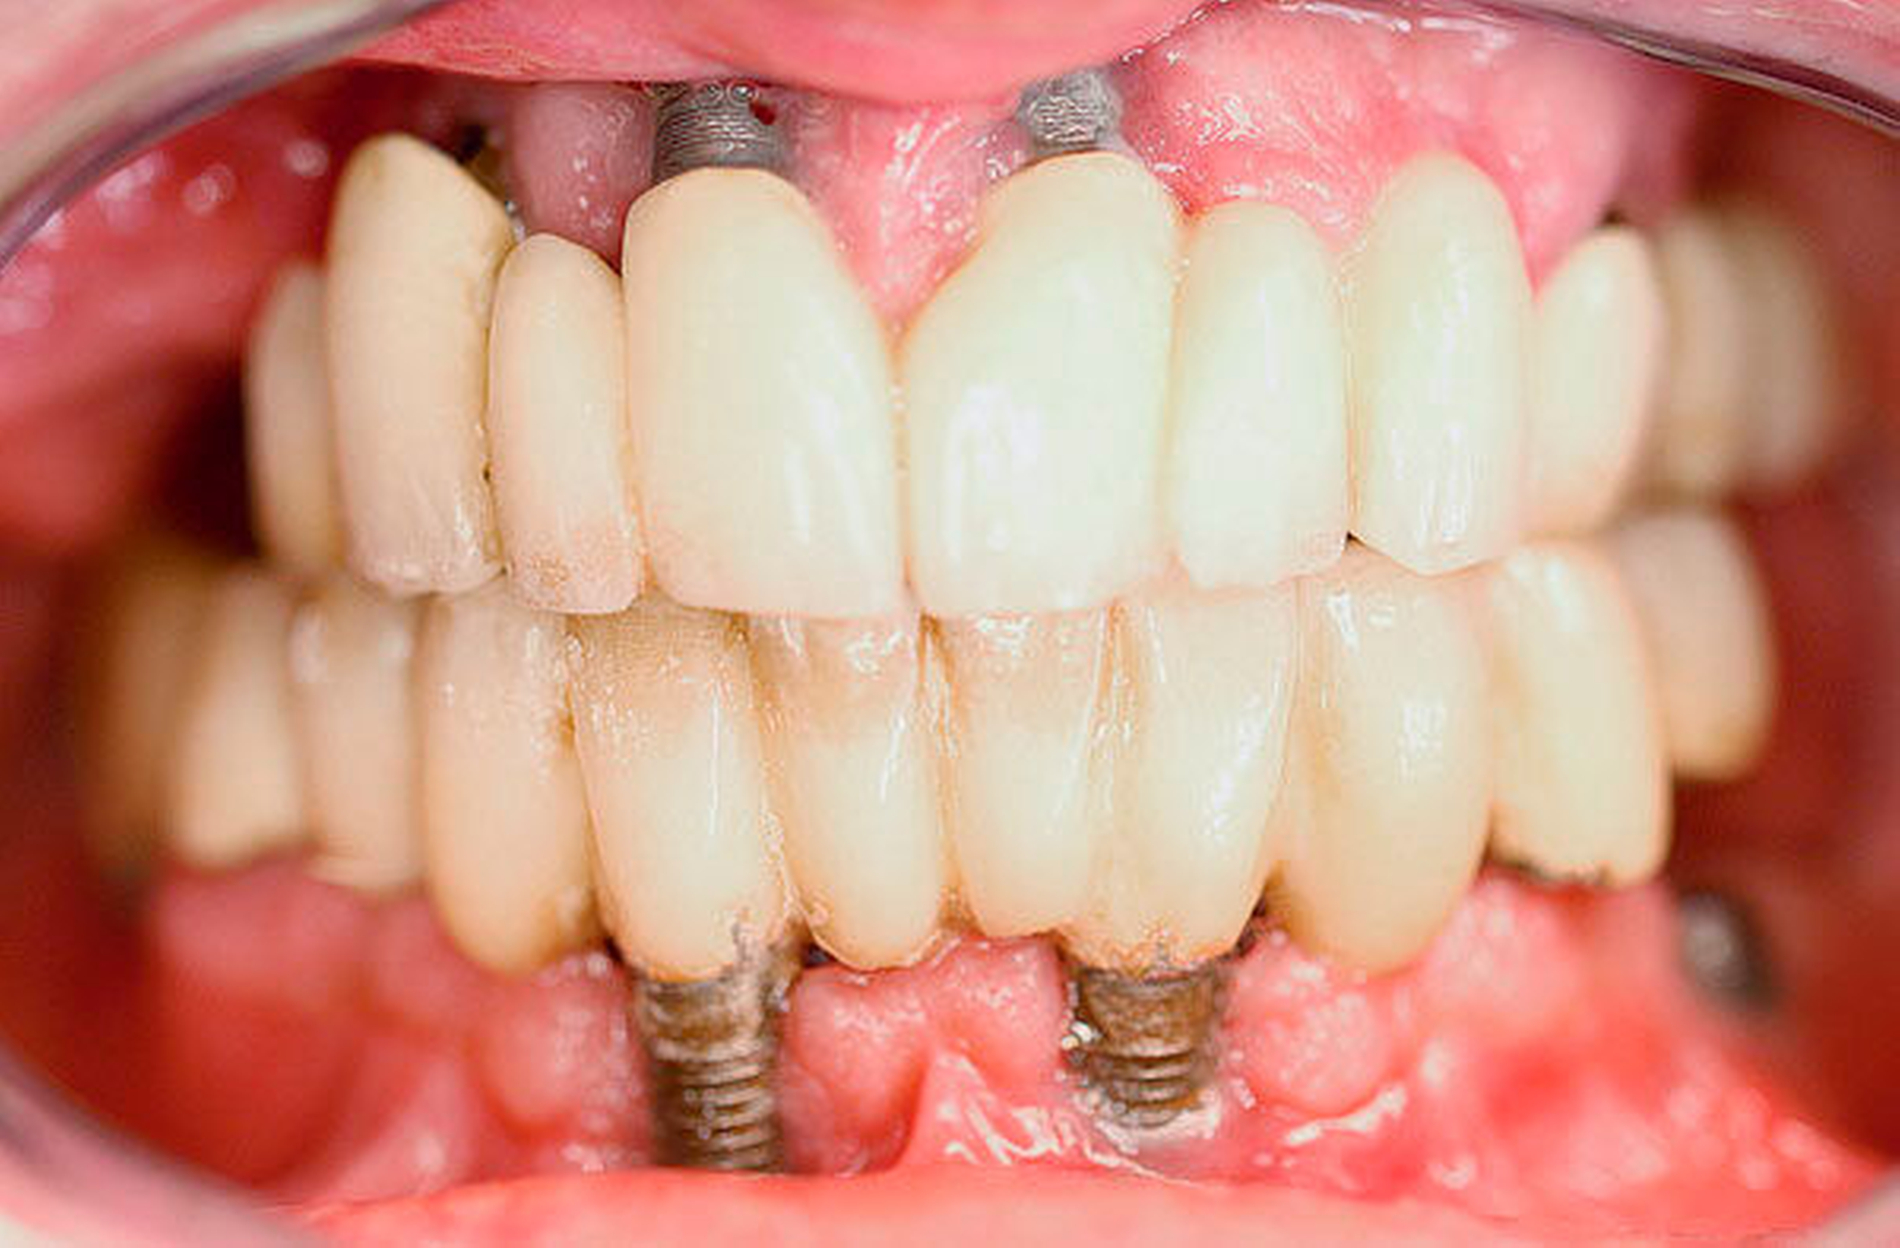

Intraoral zeigten sich implantatgetragene Kronen-Brückenkonstruktionen im Ober- und im Unterkiefer. Diese waren initial sowohl im Ober- als auch im Unterkiefer auf jeweils vier Implantaten befestigt. Im Bereich des rechten Oberkiefers zeigte sich in Regio 16 eine Mund-Antrum-Verbindung, die offenbar nach dem Versuch einer primären plastischen Deckung weiterbestand. Es bestand eine breite Dehiszenz bis ins Kieferhöhlenlumen hinein. An allen Implantaten zeigte sich eine chronische Periimplantitis mit ausgeprägtem Knochenabbau und freiliegenden oberen Gewindegängen.

Im vorliegenden Fall stellte sich der 50-jährige Patient elf Jahre nach implantatprothetischer Versorgung nach dem All-on-4 Konzept vor. Das Konzept „All-on-4“ mit einer festsitzenden Versorgung ist gut dokumentiert [Balshi et al., 2014]. Malo et al. konnten den Erfolg und die Ergebnisse über zehn Jahre verfolgen und dokumentieren [Malo et al., 2011]. Die Datenlage scheint so gut, dass das beschriebene Konzept manchen Autoren zufolge einer aufwendigen Sinuslift-Behandlung vorzuziehen ist [Asawa et al., 2015]. Bei hoch atrophierten Kiefern ist ein extralanges Zygoma-Implantat eine gute Option und kann gute Ergebnisse liefern [Brånemark et al., 2004].